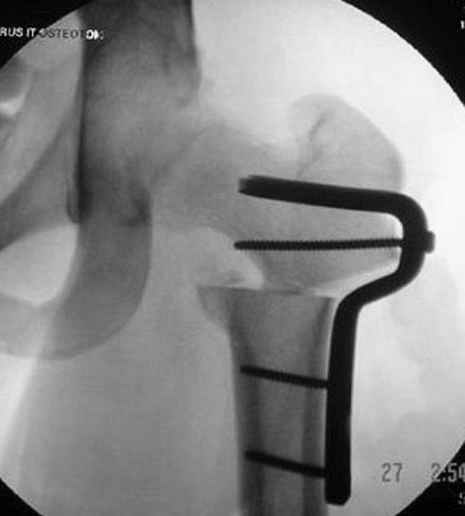

Несколько снимков из моей коллекции, чтобы разьяснить, почему мы до сих пор делаем различные варианты остеотомии.

На рисунке N1 предоперационный план лечения ложного сустава шейки бедра- линия ложного сустава, угол и направление введения импланта, клиновидная остеотомия в градусах и миллиметрах, второй снимок после коррекции, расчет, на сколько удлиняется конечность и размеры импланта;

N3 рисунок окончательный снимок, после операции моя рентгенограмма должен выглядеть примерно как эта картина. На N4 снимке клин перед удалением; N5 послеоперации 3 нед.; N6 окончательная рентгенограмма.

(доложен в Ст. Петербурге 2003 и в Москве 2004)

варус при проксимальном отделе 95 градусной пластиной.

пластическая модель; и коррекция бедра аппаратом Илизарова.